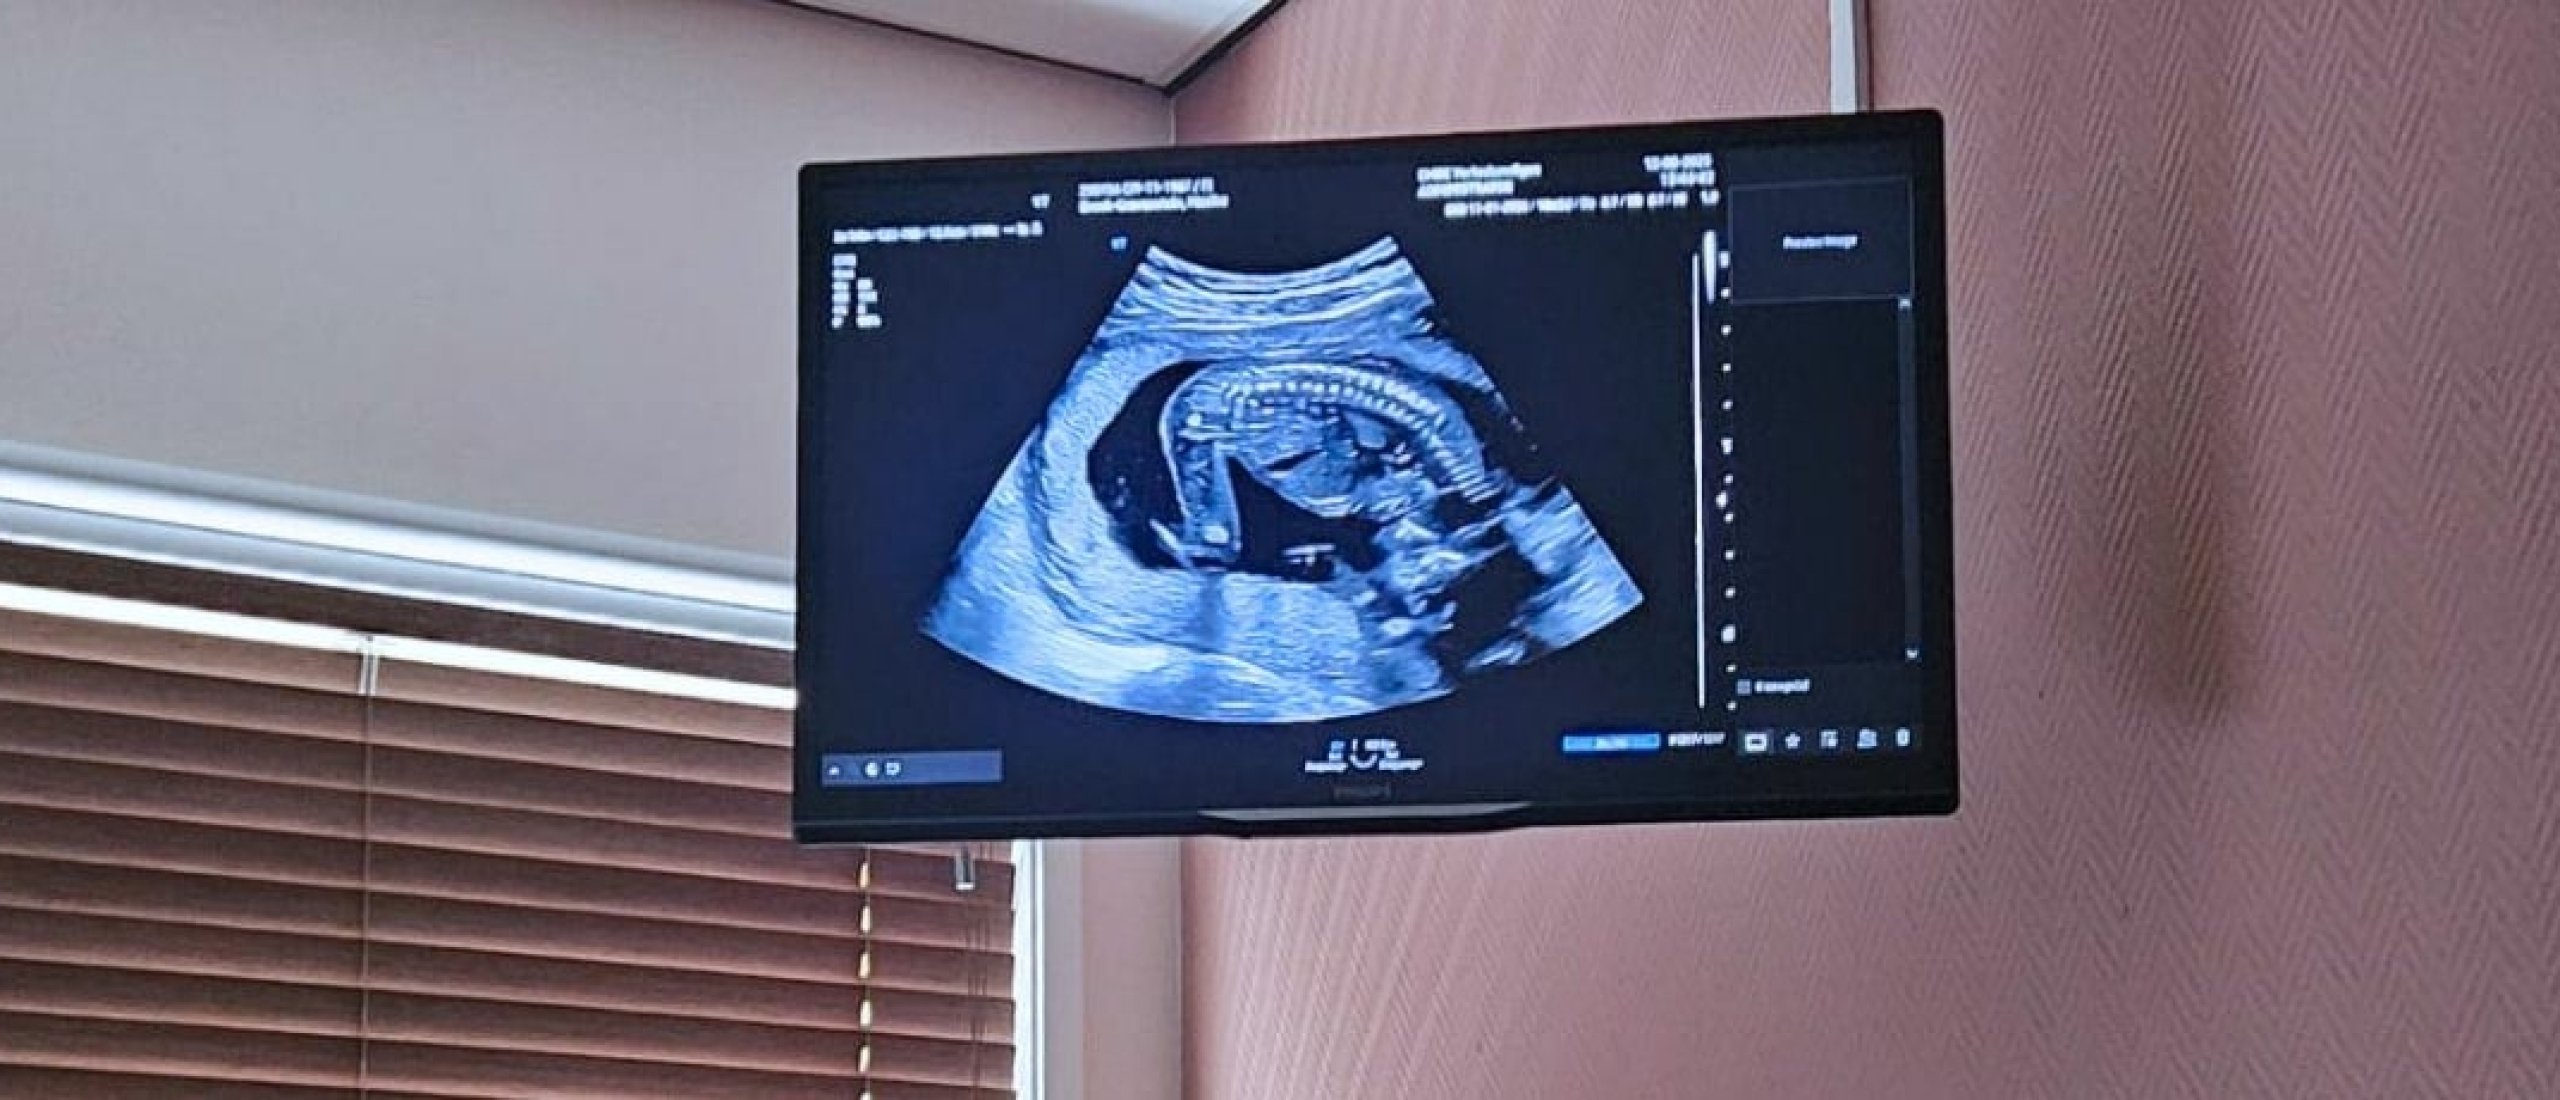

De 20 weken echo: een bijzondere mijlpaal in mijn zwangerschap

Afgelopen week hadden we onze 20 weken echo – een moment waar ik enorm naar uitkeek. Niet alleen omdat dit hét moment is waarop veel ouders het geslacht ontdekken, maar vooral omdat het een uitgebreide medische check is van ons kindje. En geloof me: er wordt een hoop bekeken!

De 20 weken echo is geen “kijk-hoe-schattig” echo, maar een medische screening. Hierbij wordt gecontroleerd of de organen zich goed ontwikkelen en of er eventueel afwijkingen zijn. Dat kan soms best spannend zijn, want er wordt echt van top tot teen gekeken.

Wat wordt er allemaal gecheckt?

Alles. Echt alles.

- Hartje (en daar was ik extra benieuwd naar)

- Nieren, maag, lever en milt

- Wervelkolom

- Buikwand (om bijvoorbeeld een open buik uit te sluiten)

- Lippen (controleren op hazenlip)

- Voetjes (klompvoeten)

- Vruchtwaterhoeveelheid

- De positie van de placenta

- Bewegingsruimte

En ja… dat is best intens, maar ook zo fascinerend. Helemaal als je zelf een medische achtergrond hebt zoals ik. Dan kijk je echt vol bewondering naar hoe perfect het lichaam zich al vormt in deze fase.

We hadden het vermoeden al, maar het was overduidelijk te zien: we verwachten een jongen!

Het was zelfs zó duidelijk, dat ik in eerste instantie dacht dat ik een uitsteeksel van de wervelkolom zag in plaats van zijn geslachtsdeel. Even verwarring – daarna vooral hilariteit.